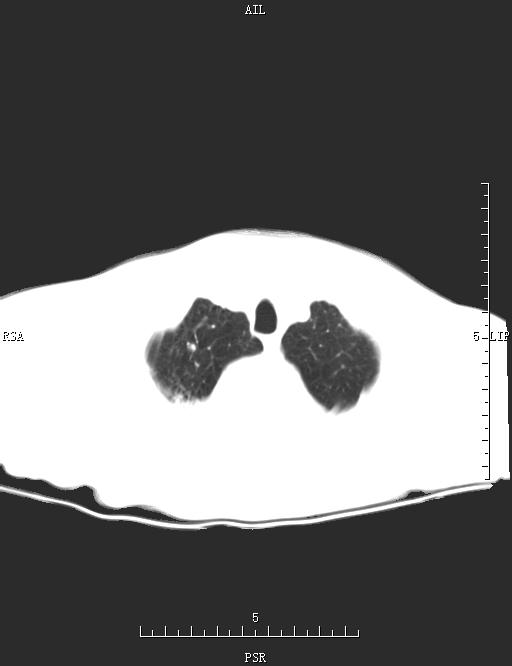

CT52434:胸部CT

男,78岁,咳嗽、咳黄痰、左侧胸痛1周。

考虑左肺舌叶继发性肺结核伴空洞形成并感染。

左后纵膈脂肪瘤。

肺脓肿;

后纵隔肿瘤.